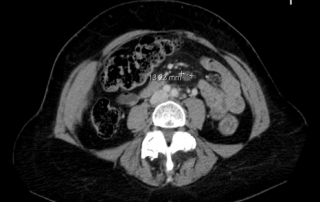

Scanner comparé au scanner avant traitement, la cible axillaire droite taille 18 x 9 mm

vs 32 x 31 mm soit une régression de 84% sur cette cible.

Les adénomégalies sous diaphragmatiques initiales sont remplacées par des

ganglions de taille normale.